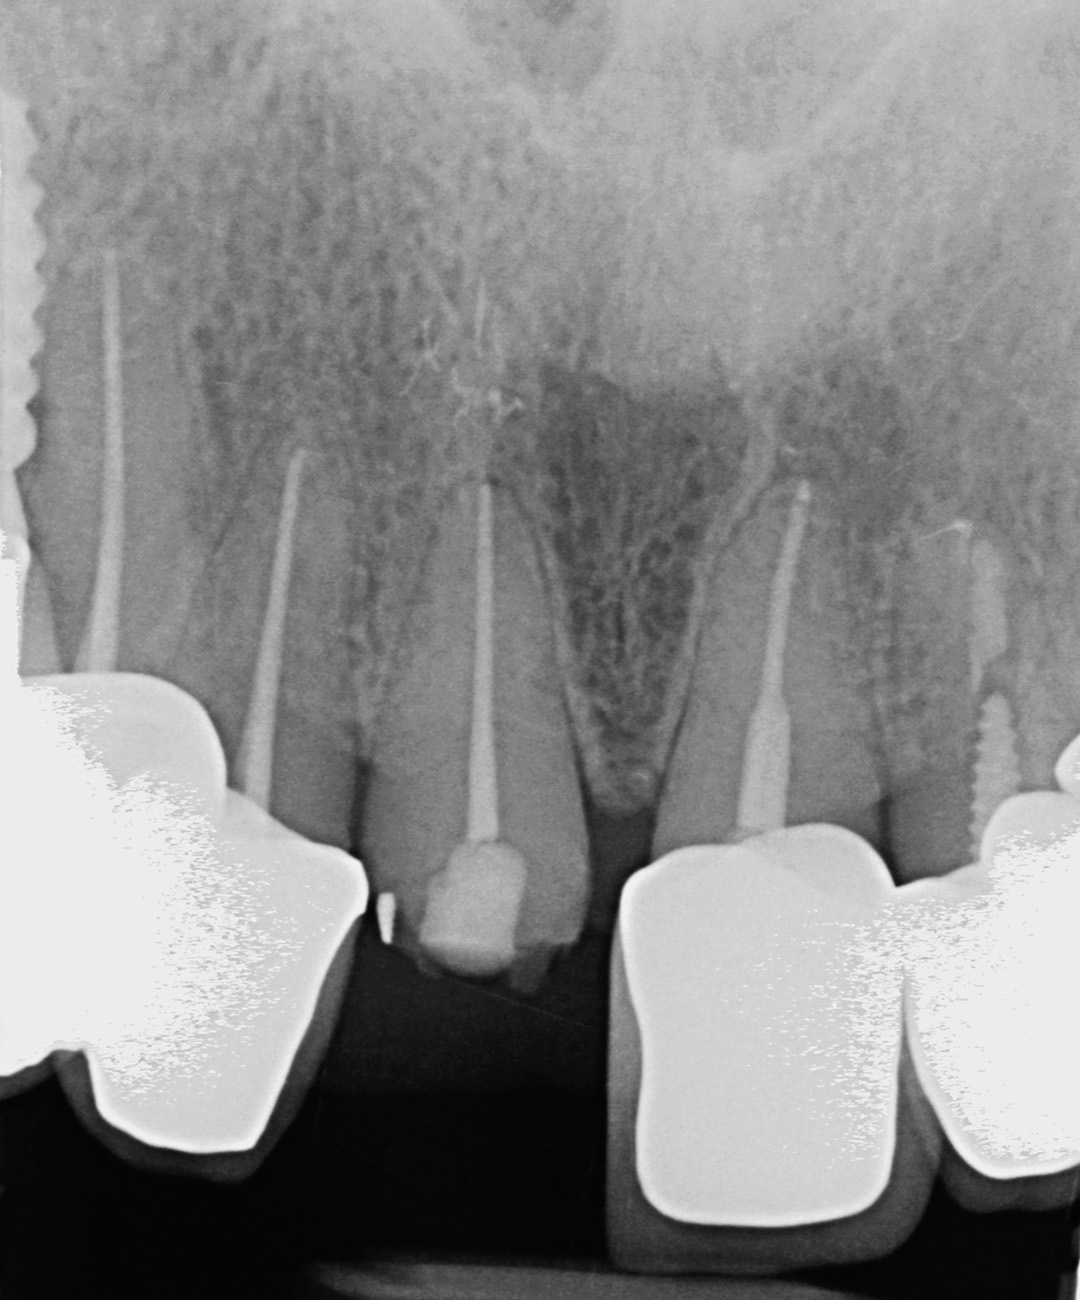

Surgery and initial outcomes

The remaining root was carefully and atraumatically extracted using a Benex® pull-out device. The surgical guide was fitted in the mouth and a CONELOG PROGRESSIVE-LINE implant with conical connection was immediately placed, torqued to above 50 Ncm for high primary stability. The space between the implant and the facial cortical bone plate was filled with MinerOss XP biomaterial and a connective tissue graft was tunnelled around the neck of the implant. This was harvested from the tuberosity, de-epithelialised, and added around the neck of the implant. The objective of this procedure was to ensure long-term papilla stability and prevent both the future collapse of the soft tissue and opening of the embrasures. This is paramount when restoring a gap in the anterior zone.